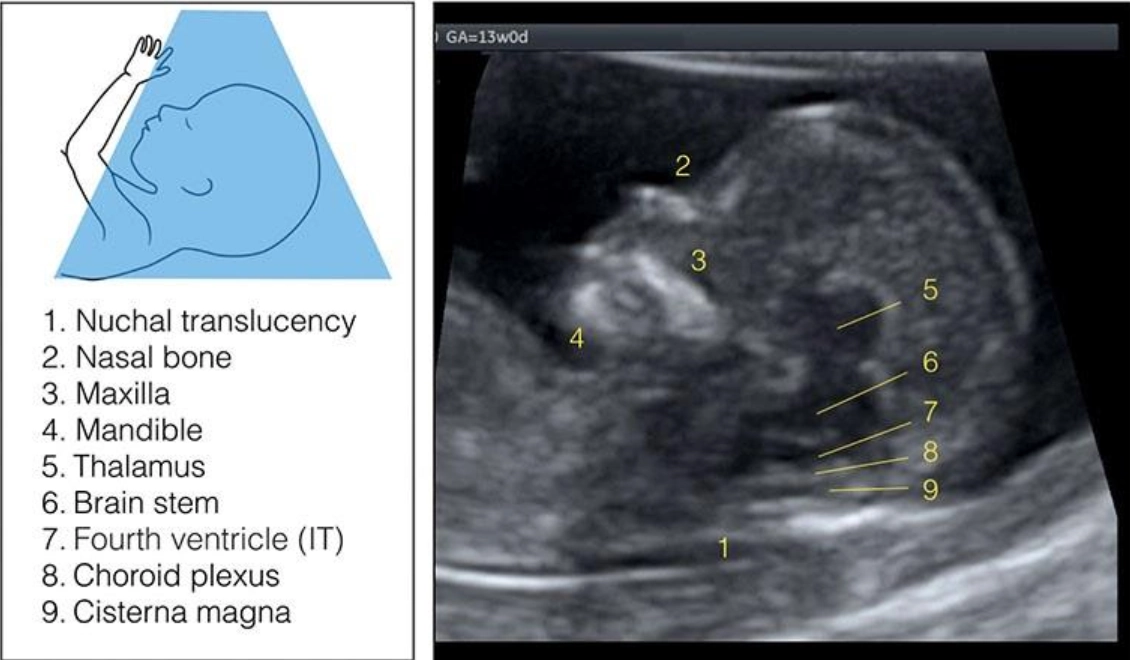

Giải phẫu bình thường hệ thần kinh trung ương thai quý I (Normal CNS anatomy in first trimester)

16/03/2026

Bất thường hố sau quý I